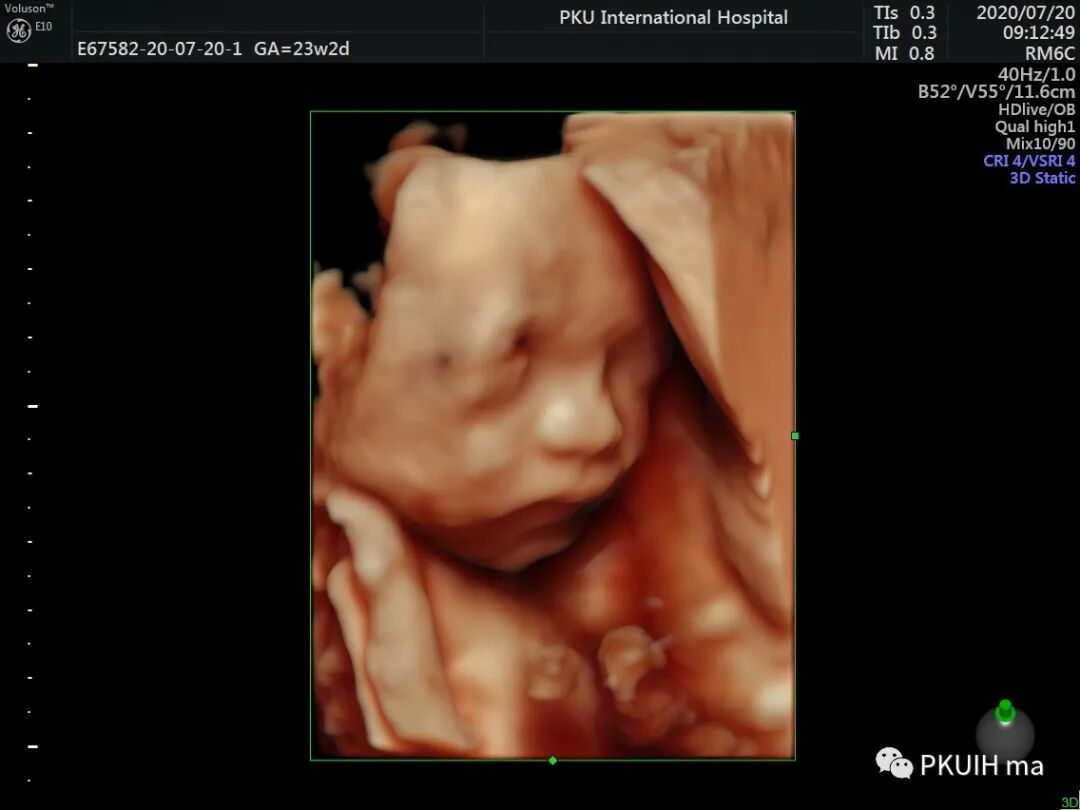

同样对于23周筛畸时三维图像热指数和机械指数是0.3和0.8,也是非常低的。所以不管在什么时段的妊娠三维四维的热指数均小于1.0,都是安全的。

小宝宝在打哈欠

在想美事

在思考或者是安静的休息